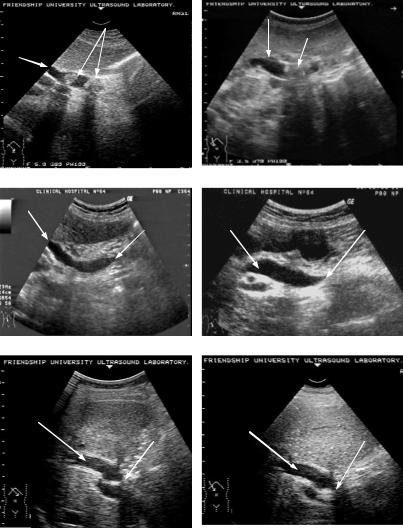

Рис. 45. Ультразвуковые томограммы при холедохолитиазе (А), стенозе БДС (Б), стриктуре желчного протока (В):

а - камень; б - желчный проток; в - зона стеноза; г - зона стриктуры